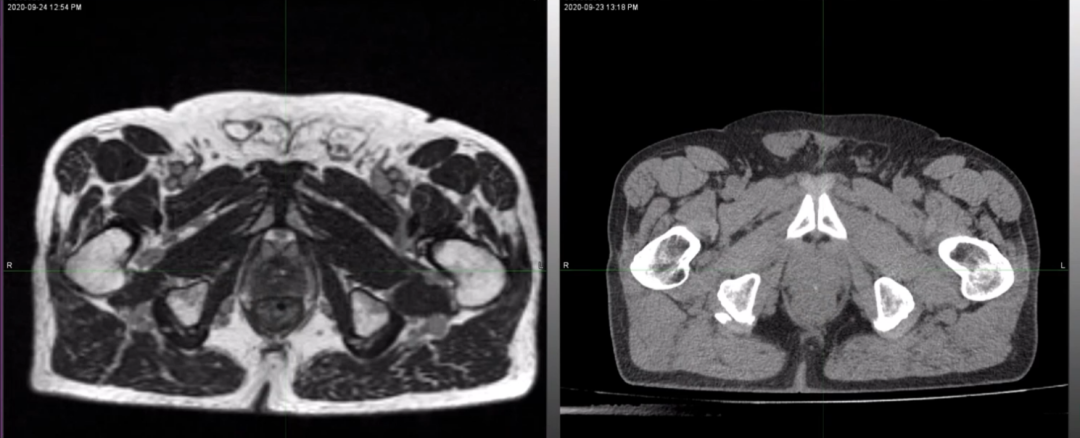

ÁíÍ⣬£¬£¬£¬£¬£¬Dr. Camilleri»¹Õ¹Ê¾ÁËһλ÷ÅÊàŦÖû»ÊõºóǰÏßÏÙ»¼ÕßMRIdian 0.35T MRIÓ°ÏñºÍCT¶¨Î»Í¼Ïñ£¬£¬£¬£¬£¬£¬MRIdian MRIͼÏñÊܽðÊô÷ÅÊàŦ¼ÙÌåÓ°Ïì½ÏС£¬£¬£¬£¬£¬£¬ÈÔÄÜ¿´Çå°ÐÇøºÍËùÓÐΣ¼°Æ÷¹Ù£¬£¬£¬£¬£¬£¬¼ûFigure 5¡£¡£¡£¡£¡£¡£¡£ÒÔÊÇ£¬£¬£¬£¬£¬£¬ÈÔÈ»ÄÜΪ»¼ÕßÌṩÖðÈÕÔÚÏß×Ô˳Ӧ·ÅÁÆÍýÏ룬£¬£¬£¬£¬£¬µ«ÖµµÃ×¢ÖØµÄÊÇ£¬£¬£¬£¬£¬£¬ÉäÊø±ØÐè±Ü¿ª½ðÊô÷ÅÊàŦ£¬£¬£¬£¬£¬£¬¼ûFigure 6¡£¡£¡£¡£¡£¡£¡£

Figure 5?Dr. CamilleriչʾµÄ÷ÅÊàŦÖû»ÊõºóǰÏßÏÙ»¼ÕßMRIdian 0.35T MRIÓ°Ïñ£¨×󣩺ÍCT¶¨Î»Í¼Ïñ£¨ÓÒ£©£¬£¬£¬£¬£¬£¬MRIdian MRIͼÏñÊܽðÊô÷ÅÊàŦ¼ÙÌåÓ°Ïì½ÏС